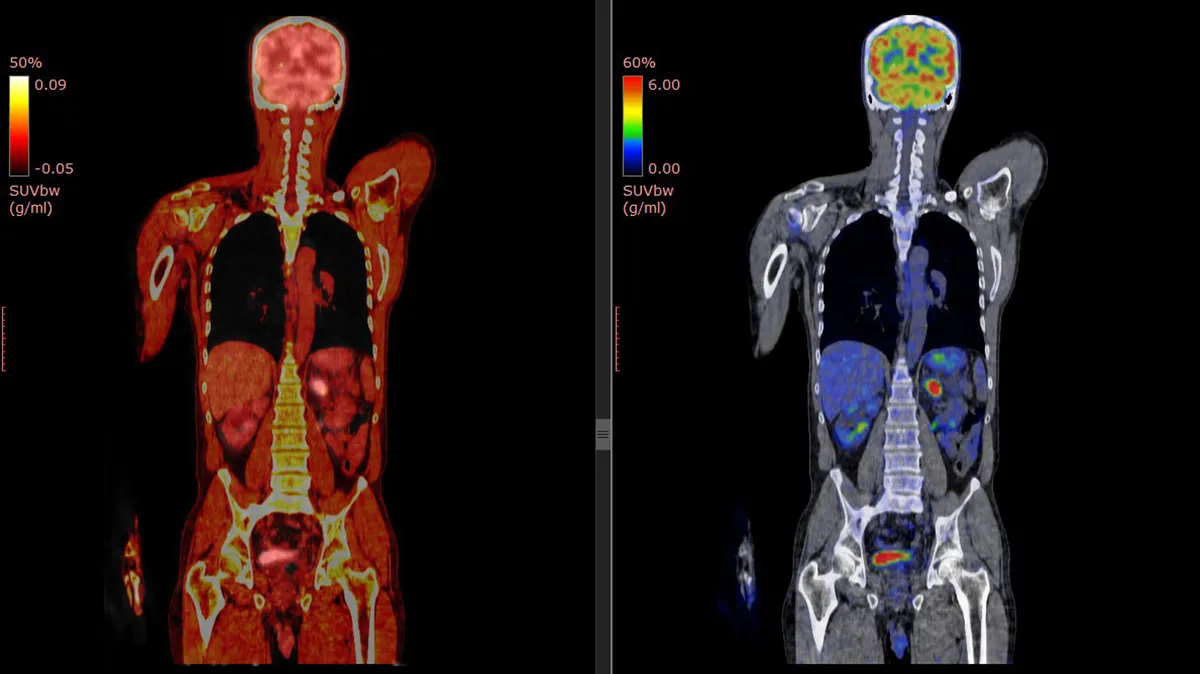

Danny Altmann, profesor de inmunología del Imperial College de Londres, coautor del Penguin Handbook of Long Covid e investigador principal del estudio NIHR WILCO LONG COVID, no participó en el estudio, pero explicó que se trata de un enfoque novedoso que permite mapear las células T activadas en el cuerpo.

“Hallaron patrones de activación de células T a largo plazo que podrían ayudar a explicar los patrones de los síntomas de Covid prolongado. Por ejemplo, las personas con síntomas respiratorios mostraron una migración prolongada de células T activadas a los pulmones”.

Otras exploraciones mostraron células T actividas que se aglomeraron en la pared intestinal, lo que llevó al equipo a estudiar biopsias intestinales. Ahí volvieron a encontrar la presencia de ARN de COVID.

Este descubrimiento fue impactante en comparación con seis muestras de control: exploraciones hechas antes de la pandemia, cuando nadie se había contagiado, como explicó Stat Michael Peluso, profesor adjunto de medicina en la Universidad de California en San Francisco, autor principal del artículo. En este caso, aunque las células T se activaron, se concentraron donde debería: el hígado, los riñones y otras zonas comunes para eliminar la inflamación. Pero en pacientes con COVID prolongado, estaban en todas partes.